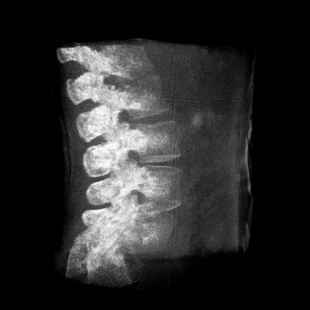

提供更大的術(shù)中三維成像視野,采集更多圖像信息,可一次拍全全段頸椎、全段腰椎、七節胸椎、雙側骶髂關(guān)節、股骨頭及單側盆骨。